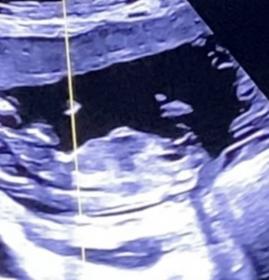

Tricky NUB 13+1 weeks? Long NUB but some stacking?

I had a scan yesterday (13+1 weeks!). During the scan I was convinced I saw long somewhat flat, but also a stacked nub (I saw a shadow in the background), but the tech said it was the stacking was the umbilical cord. The tech said she saw a flat NUB that I is why she was leaning more towards girl.

I posted my scans online and got mostly boy guesses (some girl because of the "flat" NUB) but I was wondering if it's still possible it might be a girl? That the "stacked thing" is something else??? (Already got 3 boys so a girl would be so welcome!)